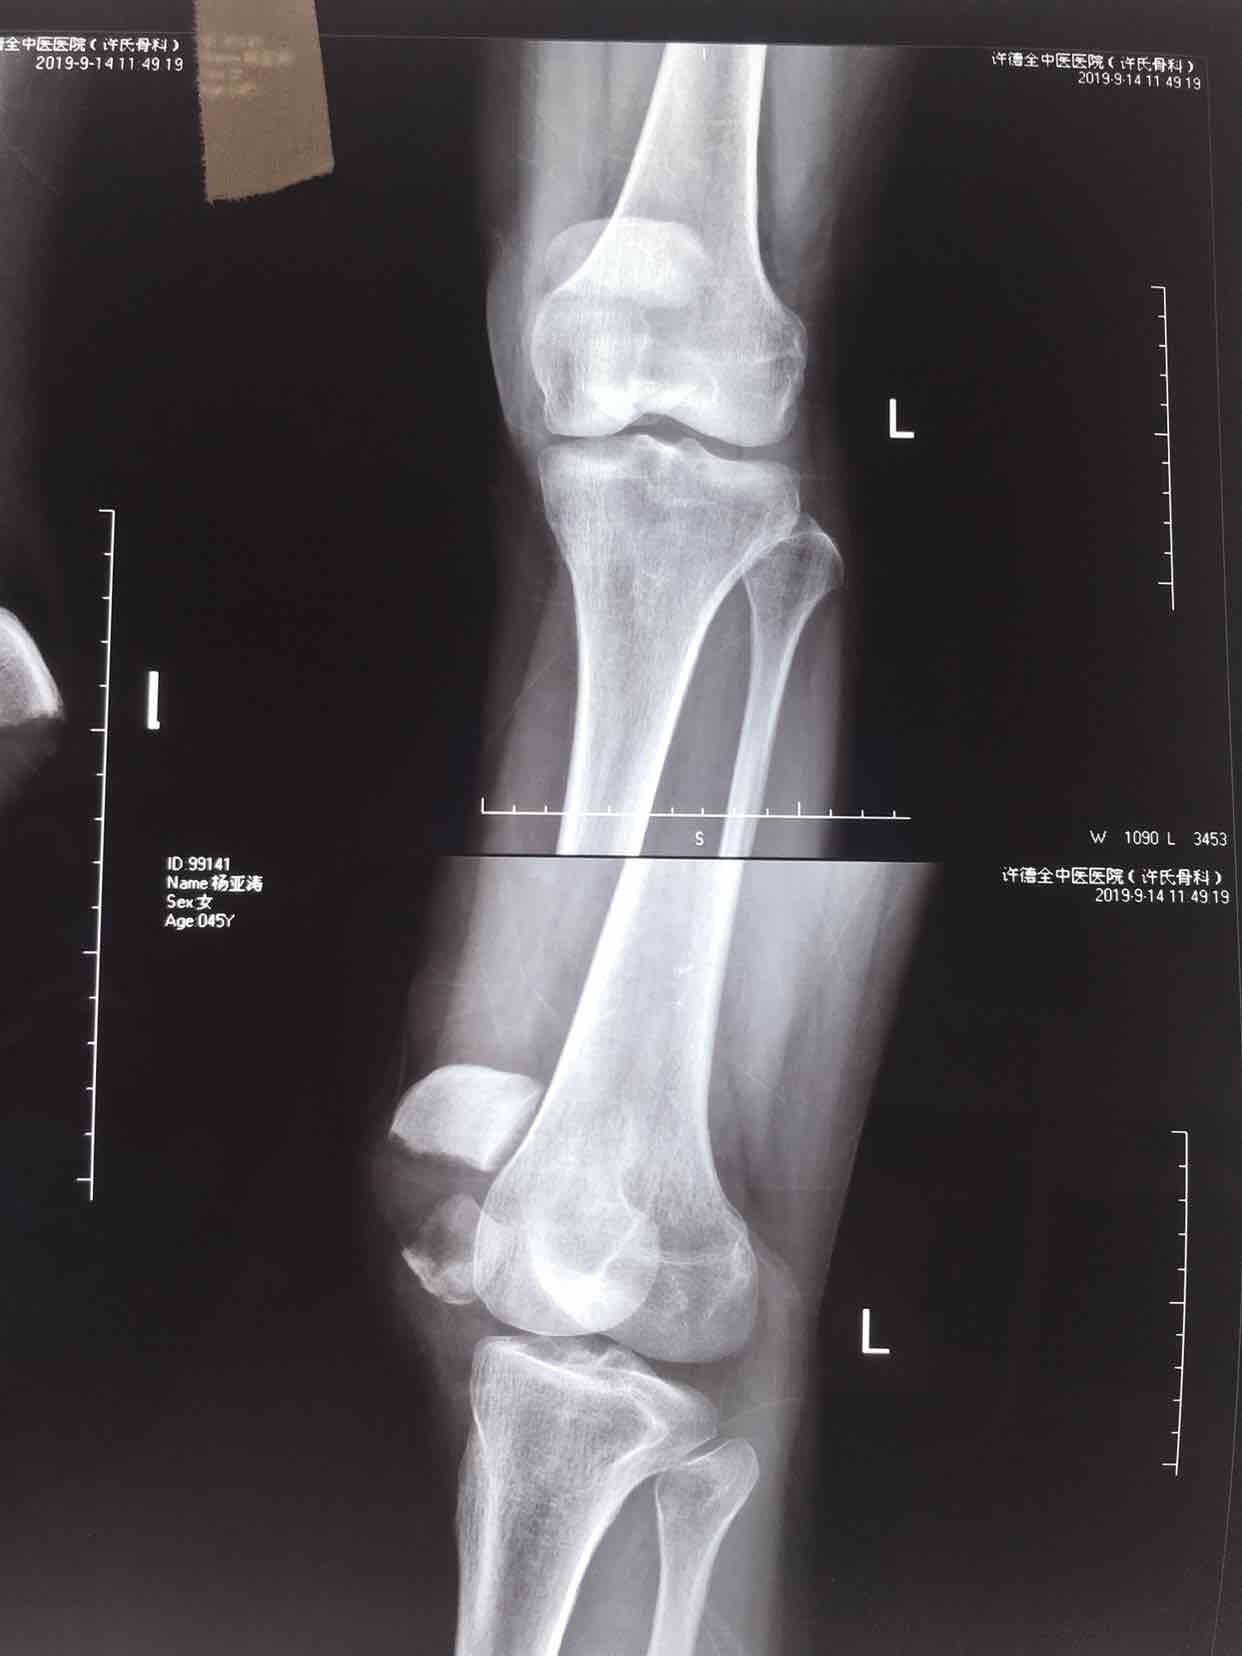

患者:女/四十五岁

摔伤后左膝部肿痛,活动受限1小时。

生命体征平稳,心肺复未见异常。左膝部肿胀明显,局部皮色皮温正常,压痛,可及骨折断端,膝关节伸膝受限,末梢血运感觉正常。

诊断左髌骨粉碎性骨折